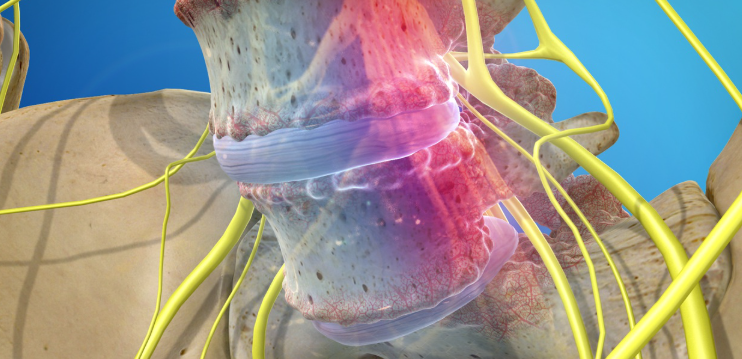

척추 전방전위증은 척추의 특정 마디가 제자리에서 앞으로 밀려나면서 신경을 압박하는 질환입니다. 주로 요추 4번과 5번 사이에서 자주 발생하며, 심한 경우에는 허리 통증뿐 아니라 다리 저림, 감각 이상, 보행 불편 등의 신경 증상이 동반될 수 있습니다.

척추는 여러 개의 뼈(척추체)와 디스크, 인대, 근육이 정교하게 맞물려 안정성을 유지하는데, 이 중 하나라도 약해지면 구조적 불균형이 생기게 됩니다. 척추 전방전위증은 이 균형이 무너진 대표적인 예로, 척추를 잡아주는 심부근육이 약화된 상태에서 자주 나타납니다.

2. 신경 압박의 영향

척추 전방전위증의 진행이 심하면 척추관이 좁아지면서 좌골신경통 같은 신경성 통증이 동반되기도 합니다. 이는 단순히 허리 근육 문제를 넘어선 신경적 불편함으로 이어질 수 있어 조기 관리가 중요합니다.